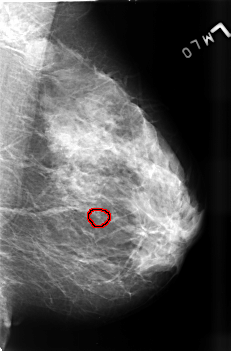

B_3456_1.LEFT_MLO

LEFT_MLO LINES 4552 PIXELS_PER_LINE 2992 BITS_PER_PIXEL 12 RESOLUTION 50 OVERLAY

FILE: B_3456_1.LEFT_MLO.OVERLAY

TOTAL_ABNORMALITIES 1

ABNORMALITY 1

LESION_TYPE CALCIFICATION TYPE PLEOMORPHIC DISTRIBUTION CLUSTERED

ASSESSMENT 4

SUBTLETY 3

PATHOLOGY BENIGN

TOTAL_OUTLINES 1

BOUNDARY